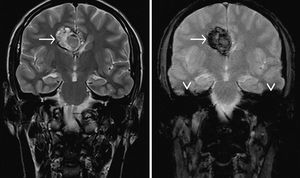

Cerebral cavernous venous malformations, commonly known as cavernous haemangioma or cavernoma, are common cerebral vascular malformations, usually with characteristic appearances on MRI. MRI is the modality of choice, demonstrating a characteristic “popcorn” or "berry" appearance with a rim of signal loss due to hemosiderin, which demonstrates prominent blooming on susceptibility weighted sequences. T1 and T2 signal is varied internally depending on the age of the blood produces and small fluid-fluid levels may be evident. Gradient echo or T2* sequences are able to delineate these lesions better than T1 or T2 weighted images. In patients with familial or multiple cavernous angiomas GRE T2* sequences are very important in identifying the number of lesions missed by conventional Spin echo sequences. Note the susceptibility artifact (arrowhead) on T2*-w (right image) due to local inhomogeneities.